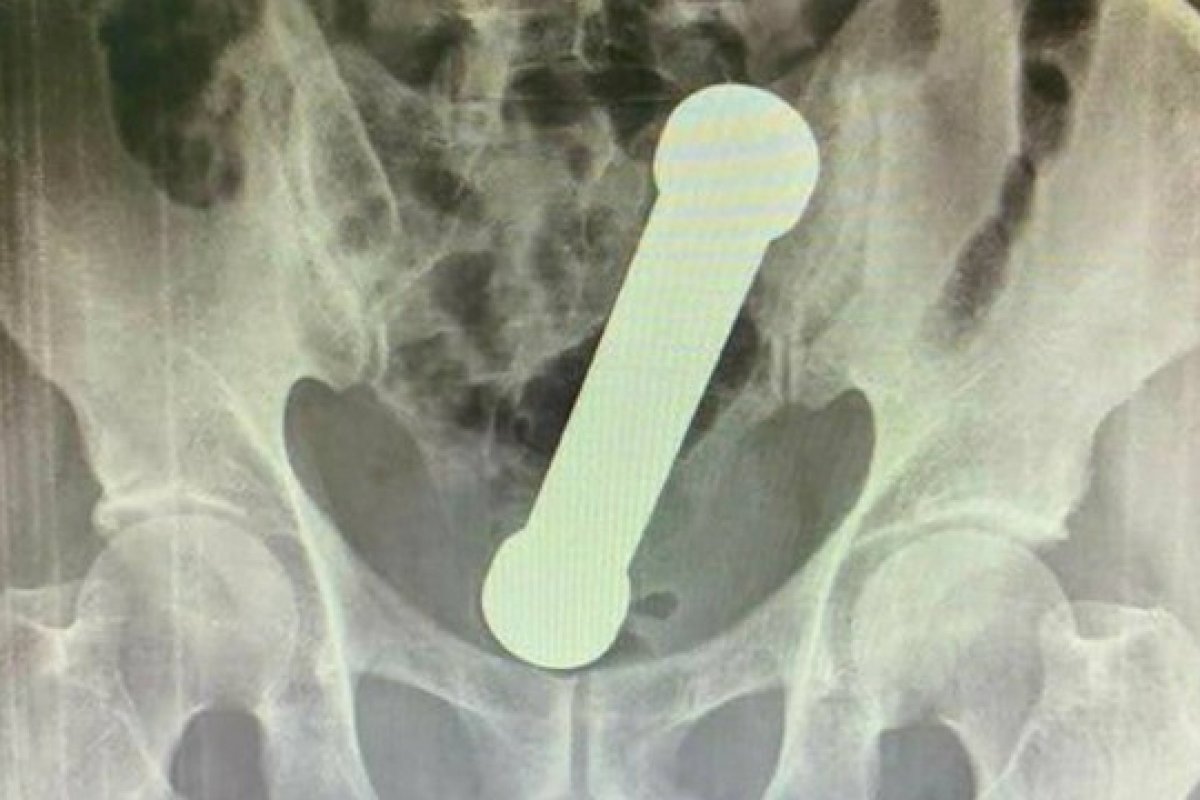

Apresentando dores no estômago e dificuldade de evacuação, um homem de 57 anos procurou um hospital da capital amazonense, onde foi encaminhado para realizar algumas radiografias. Ao examinar as imagens, os médicos constataram que havia um peso de academia dentro do paciente.

O artigo foi intitulado de 'Manejo de corpo estranho retal incomum'. Nele, os autores descrevem em detalhes os procedimentos realizados para extrair o haltere de 20cm do corpo do homem.